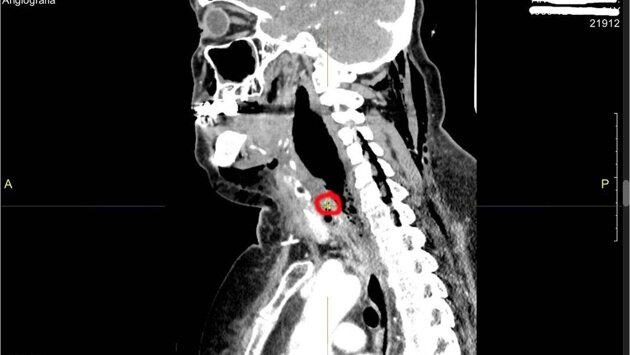

В областную больницу пациентка поступила в тяжелом состоянии с сильнейшим обезвоживанием и интоксикацией. При проведении компьютерной томографии было обнаружено инородное тело шейного отдела пищевода (рыбная кость) и флегмона шеи верхнего средостения. Гнойное воспаление тканей опустилось вниз - в полость между лёгким и сердцем, развился передний медиастинит.